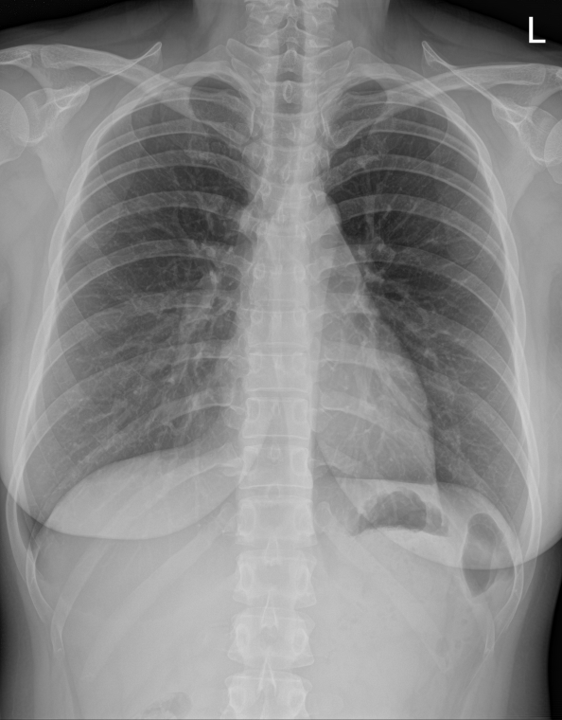

후자의 경우는 사족이 붙어야 한다. 실제로 폐렴이 있어도 엑스레이 상에서 잘 확인이 어려운 경우가 아주 많고, 진행되는 폐렴에서는 아직 영상의학적인 변화가 나타나기 전인 상황이 많아서, 폐렴이 아니라고 확신하는 건 정말 쉽지 않다. 아래 사진을 보자.

이 두 사진은 모두 같은 환자의 다른 날짜에 촬영된 흉부 엑스레이다. 좌우 사진 중 어떤 사진이 더 회복된 상황일까? 우측 사진이다. 잘 보면 우측보다 좌측 음영이 조금 더 blunt 해 보이는 것을 알 수 있다. 사실 이 정도면 의사들 사이에서도 과에 따라서 둘 다 정상, 둘 다 이상, 한쪽만 이상 등으로 갈릴 수 있을 정도의 사진이다.